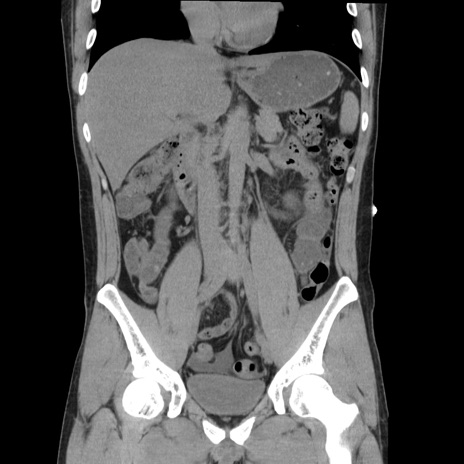

症例36(冠状断像)

【症例】20歳代 男性

【主訴】心窩部痛

【現病歴】今朝より上腹部痛あり。一旦軽快していたが再度出現したため救急要請。昨日夕に白身の魚を含む刺身を食べた。

【身体所見】BP 136/89mmHg、HR 74/min、BT 37.0℃、腹部:膨満、軟、心窩部に圧痛あり。反跳痛なし、筋性防御なし、腸雑音やや亢進あり。

【データ】WBC 17700、CRP 0.48